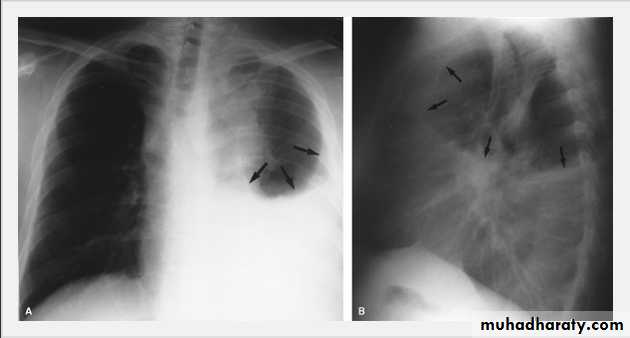

Pleural Effusion on Chest Radiographs.

Posteroanterior (A) and lateral (B) chest radiographs demonstrate the typical meniscoid appearance (arrows) in a patient with a left pleural effusionHydropneumothorax.